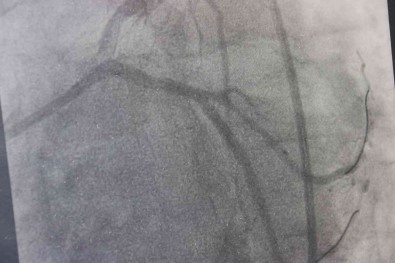

Trans yaglarin özelliklerinden dolayi endüstride son derece ragbet gördügünü aktaran Doç. Dr. Akdag, “Biz, istemiyoruz. Çünkü trans yaglar insan vücudundaki dogal yag grubundan çok farkli. Trans yaglar özellikle damarin endotel dedigimiz en önemli kismini bozan bir madde. Dolayisiyla trans yaglar damar yapilarini bozdugu için basta kalp ve beyin olmak üzere vücudun birçok organina zarar vermekte. Bununla beraber birçok kanserin olusumuna yol açabilmekte. Obeziteye, seker ve kolesterol degerlerimizi artirabilmekte. Bu nedenler dolayi biz, trans yaglarin kullanimini istemiyoruz. Trans yaglar 1911 yilinda maalesef hayatimiza girdi. O günden bugüne giderek tüketimi artmakta” dedi.

Trans yaglarla ilgili su anda Dünya Saglik Örgütünün de de devam eden bir projesi oldugunu hatirlatan Akdag, “Yerine koyma projesidir. Amaç da su, trans yaglarin endüstride tamamen sifirlanmasi, hiç kullanilmamasi. Kullanilacaksa maksimum yüzde 2 oraninda kullanilmasi. Biz, yüzde 2’ninde kullanilmasini istemiyoruz. Çünkü yapilan çalismalarda bu yüzde 2 bile kullanilirsa bu saydigimiz hastaliklara neden olabilmekte. Özellikle kalp krizi riskimiz yüksek oluyor trans yaglarla ilgili. Yapilan bir çalismada günde 5 gram üzerinde trans yag kullaniminin kalp krizi riskini yüzde 25 artirdigi saptanmis. Çocuklar özellikle bu fastfood gida tüketimi bu orani ciddi bir sekilde artirmakta. Fastfood gidalarda çok fazla trans yag kullanilmakta. Bir avuç kizarmis patateste 8 gram trans yag bulunmakta. Bunun 5 gram üzerinde olmasi kriz riskini yüzde 25 artirmakta” diye konustu.